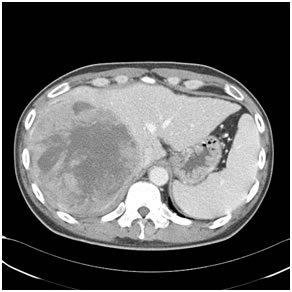

Hepatocellular Carcinoma (HCC)

A primary liver cancer seen mostly due to alcohol, Hepatitis B and C. Almost 80% are unresectable due to advanced cirrhosis or extra hepatic disease. Till date liver resection is the mainstay of the therapy and ranges from segmentectomies to major lobar resection based upon the size & location of the tumour as well as the volume & quality of theresidual liver. Local ablative procedure like radiofrequency ablation is done mainly for smaller tumors where in a resection cannot be done for various reasons. Other therapies like chemoembolization ,radioembolization and portal vein embolization may be required on case to case basis. Median 5 years survival for resected patients is about 30%. A small subset of patients are candidates for Liver transplant.

HCC in a non cirrhotic liver